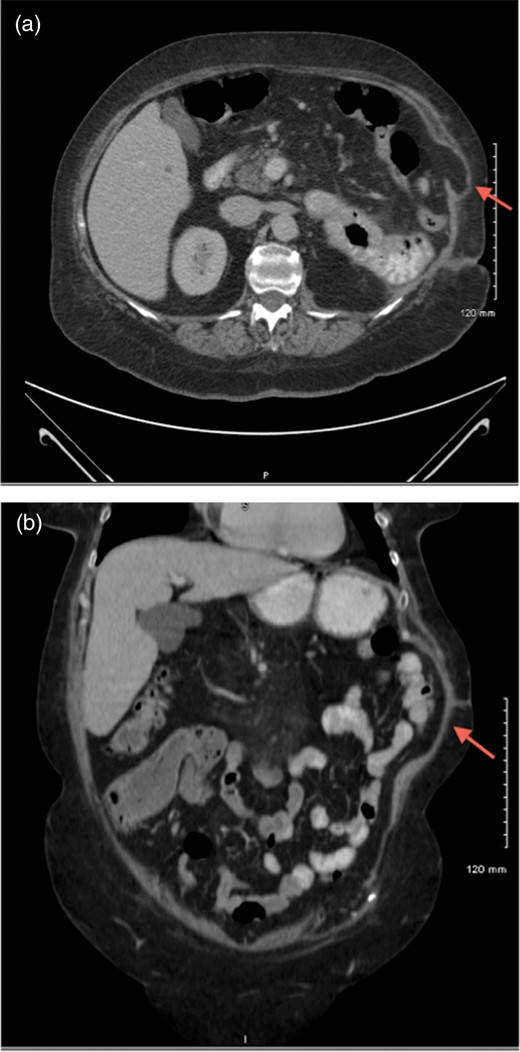

A 65-year-old female presented with a chief concern of left abdominal wall pain and possible incisional hernia. She had undergone a left radical nephrectomy, splenectomy and distal pancreatectomy earlier in the year for a mass on the left kidney. Pathologic evaluation revealed the mass to be a large perinephric abscess of uncertain etiology. Her recovery was complicated by a wound infection and development of a pancreatic fistula, which was repaired. A few months later, after recovery, the patient began experiencing significant pain at the incision site, which was worse with daily activity. She denied any symptoms of infection, such as fever or chills. A complete blood count performed shortly after surgery revealed no leuckocytosis. She was referred to general surgery for a suspected incisional hernia. Physical examination revealed a firm bulge at the superior aspect of the incision in the left upper quadrant, which was tender to palpation and non-reducible. There was no erythema, fluctuance or other signs of infection. An abdominal computed tomography (CT) scan revealed muscular laxity and a questionable abdominal wall hernia at the incision site (Fig. 1). The patient was taken to the operating room for abdominal wall wound exploration and possible hernia repair. The superior aspect of the previous incisional scar was reopened and dissection carried down through the subcutaneous tissue to the level of the fascia. No fascial defect was found; however, a firm mass was palpated within the abdominal wall. Further dissection revealed a malpositioned left rib surrounded by fibrous tissue. The rib appeared devitalized, thin and fragile. We then referred back to the CT scan and in this location, no calcification could be observed. However, this was clearly a rib. The rib was dissected until a healthy portion was noted and the devitalized rib was resected (Fig. 2). The wound was surveyed again for any muscular or fascial defects, none were found. The patient was discharged in good condition the same day. Removal of the rib sequestrum resolved the patient's symptoms.

CT scans of abdomen showing a potential abdominal wall hernia (arrows).